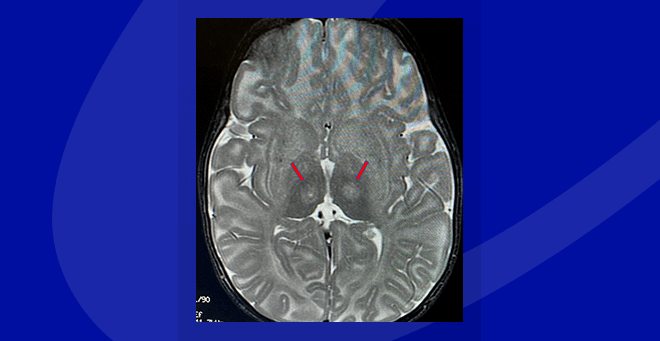

In the current study, using a hybrid approach, two harmless viral vectors were administered through injections to the thalamus and the spinal cord. These vectors deliver DNA instructions to brain cells that teach them how to produce the missing HexA enzyme. Once inside the nucleus, the vector-delivered DNA stays in the cells, allowing for long-term production of the enzyme.

The current study included nine participants in four cohorts, with the administered dosage doubling for every cohort.